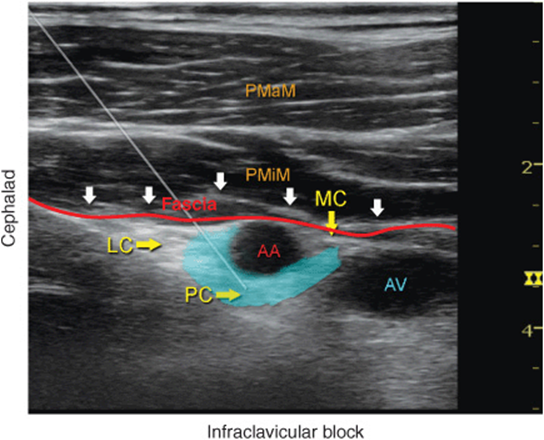

FIGURE 31-6. Ultrasound image demonstrating an ideal needle path for the infraclavicular brachial plexus block. Blue-shaded area mimics an ideal spread of the local anesthetic around axillary artery (AA) and reaching all three cords of the brachial plexus (LC, PC, MC) below the fascia (red line) of the pectoralis minor muscle. PMaM, pectoralis major muscle; PMiM, pectoralis minor muscle.